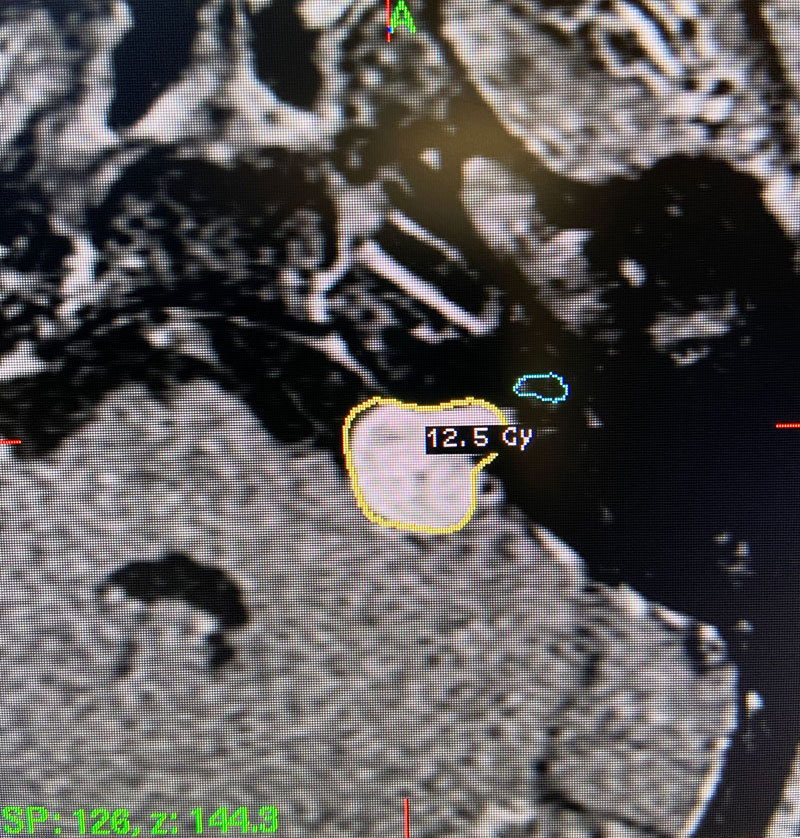

Image 1: Pre-operative imaging of the left acoustic neuroma.

Image 2: Intra-operative Gamma Knife treatment planning for the left acoustic neuroma. A tightly conformal treatment is set for 12.5Gy to the 50% isodose line. The cochlea has also been contoured, based off a fused image from a fine cut T2 sequence.

This patient: This patient had a moderate sized , symptomatic acoustic neuroma with serviceable hearing. Gamma Knife was recommended. A Gamma Knife treatment was performed by Dr. Michael Brisman. The radiation oncologist was Dr. Leester Wu. A treatment plan was made that was very conformal to the tumor. A prescription of 12.5Gy to the 50% isodose line was delivered. This plan involved a mean cochlear dose of 3.5Gy.

Technical Aspects of Gamma Knife Treatment: Dose to the tumor is set to 12-13 Gy to the edge of the tumor. The 50% isodose line is set to the edge of the tumor. Dosing under 12Gy is less effective at tumor control, and dosing over 13Gy puts the facial nerve at risk. There is evidence that the radiation dose to the cochlea affects whether hearing will ultimately be preserved. As such, if there is meaningful hearing at the time of treatment, the mean cochlear dose should be set to 4.2Gy or less. The cochlea is separately contoured at the time of treatment off fine cut T2 sequences which are then fused to the post contrast T1 images.

This is a 55 year old woman with a history of hypertension who sought attention because of one year of progressive hearing loss in the left ear. The hearing in that ear was now about 50% of normal. She also had ringing in the left ear (tinnitus). She had no problems with her right ear. Her balance was normal and she had no other complaints. Formal audiology testing confirmed hearing loss in the left ear only. MRI with and without gadolinium demonstrated a 1.3 cm solid mass in the left cerebello-pontine angle and internal auditory canal that showed homogeneous enhancement, consistent with an acoustic neuroma.